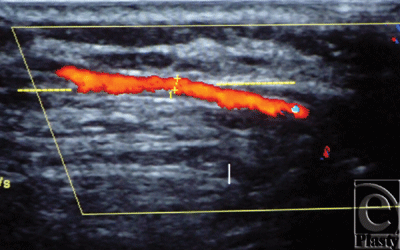

The site of the detectable perforator(s) was projected by a colored marker on the patient's skin so as to estimate the label remoteness (representing the perforation site) from the sternum (Fig 2), and the number of encountered perforators parasternally in each investigated space was counted as well. The inner diameter of each perforator was measured (Fig 3). Figures 4 to 8 show color duplex photos for perforators penetrating the fascia to reach the dermoglandular target.

| Figure 3. Color Duplex photo shows the diameter and depth of a certain visualized 5th internal mammary artery perforator from the skin surface. The point of measurement was at the perforation point. |

![]() |